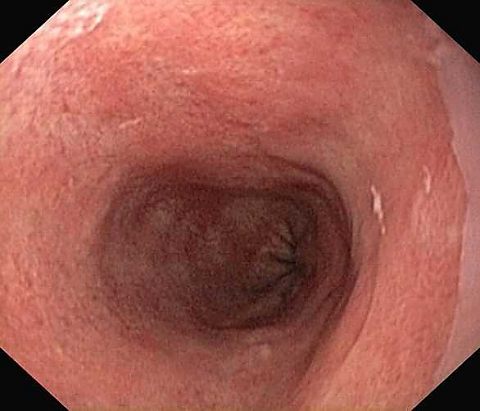

Reflux oesophagitis grade C-D according to the Los Angeles classification

Reflux oesophagitis grade D according to the Los Angeles classification